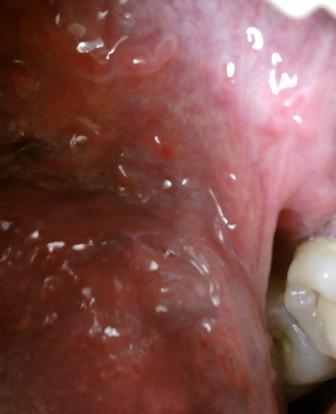

石家庄九州皮肤病医院 > 尖锐湿疣 > > > 咨询专家:尖锐湿疣不治疗会怎样很多尖锐湿疣患者由于在初期,对于病情并不是很了解,因此没有得到及时的诊治,专家表示:尖锐湿疣如果不及时诊治。病情就会加重,湿疣体体积会增大,数目也会增多。